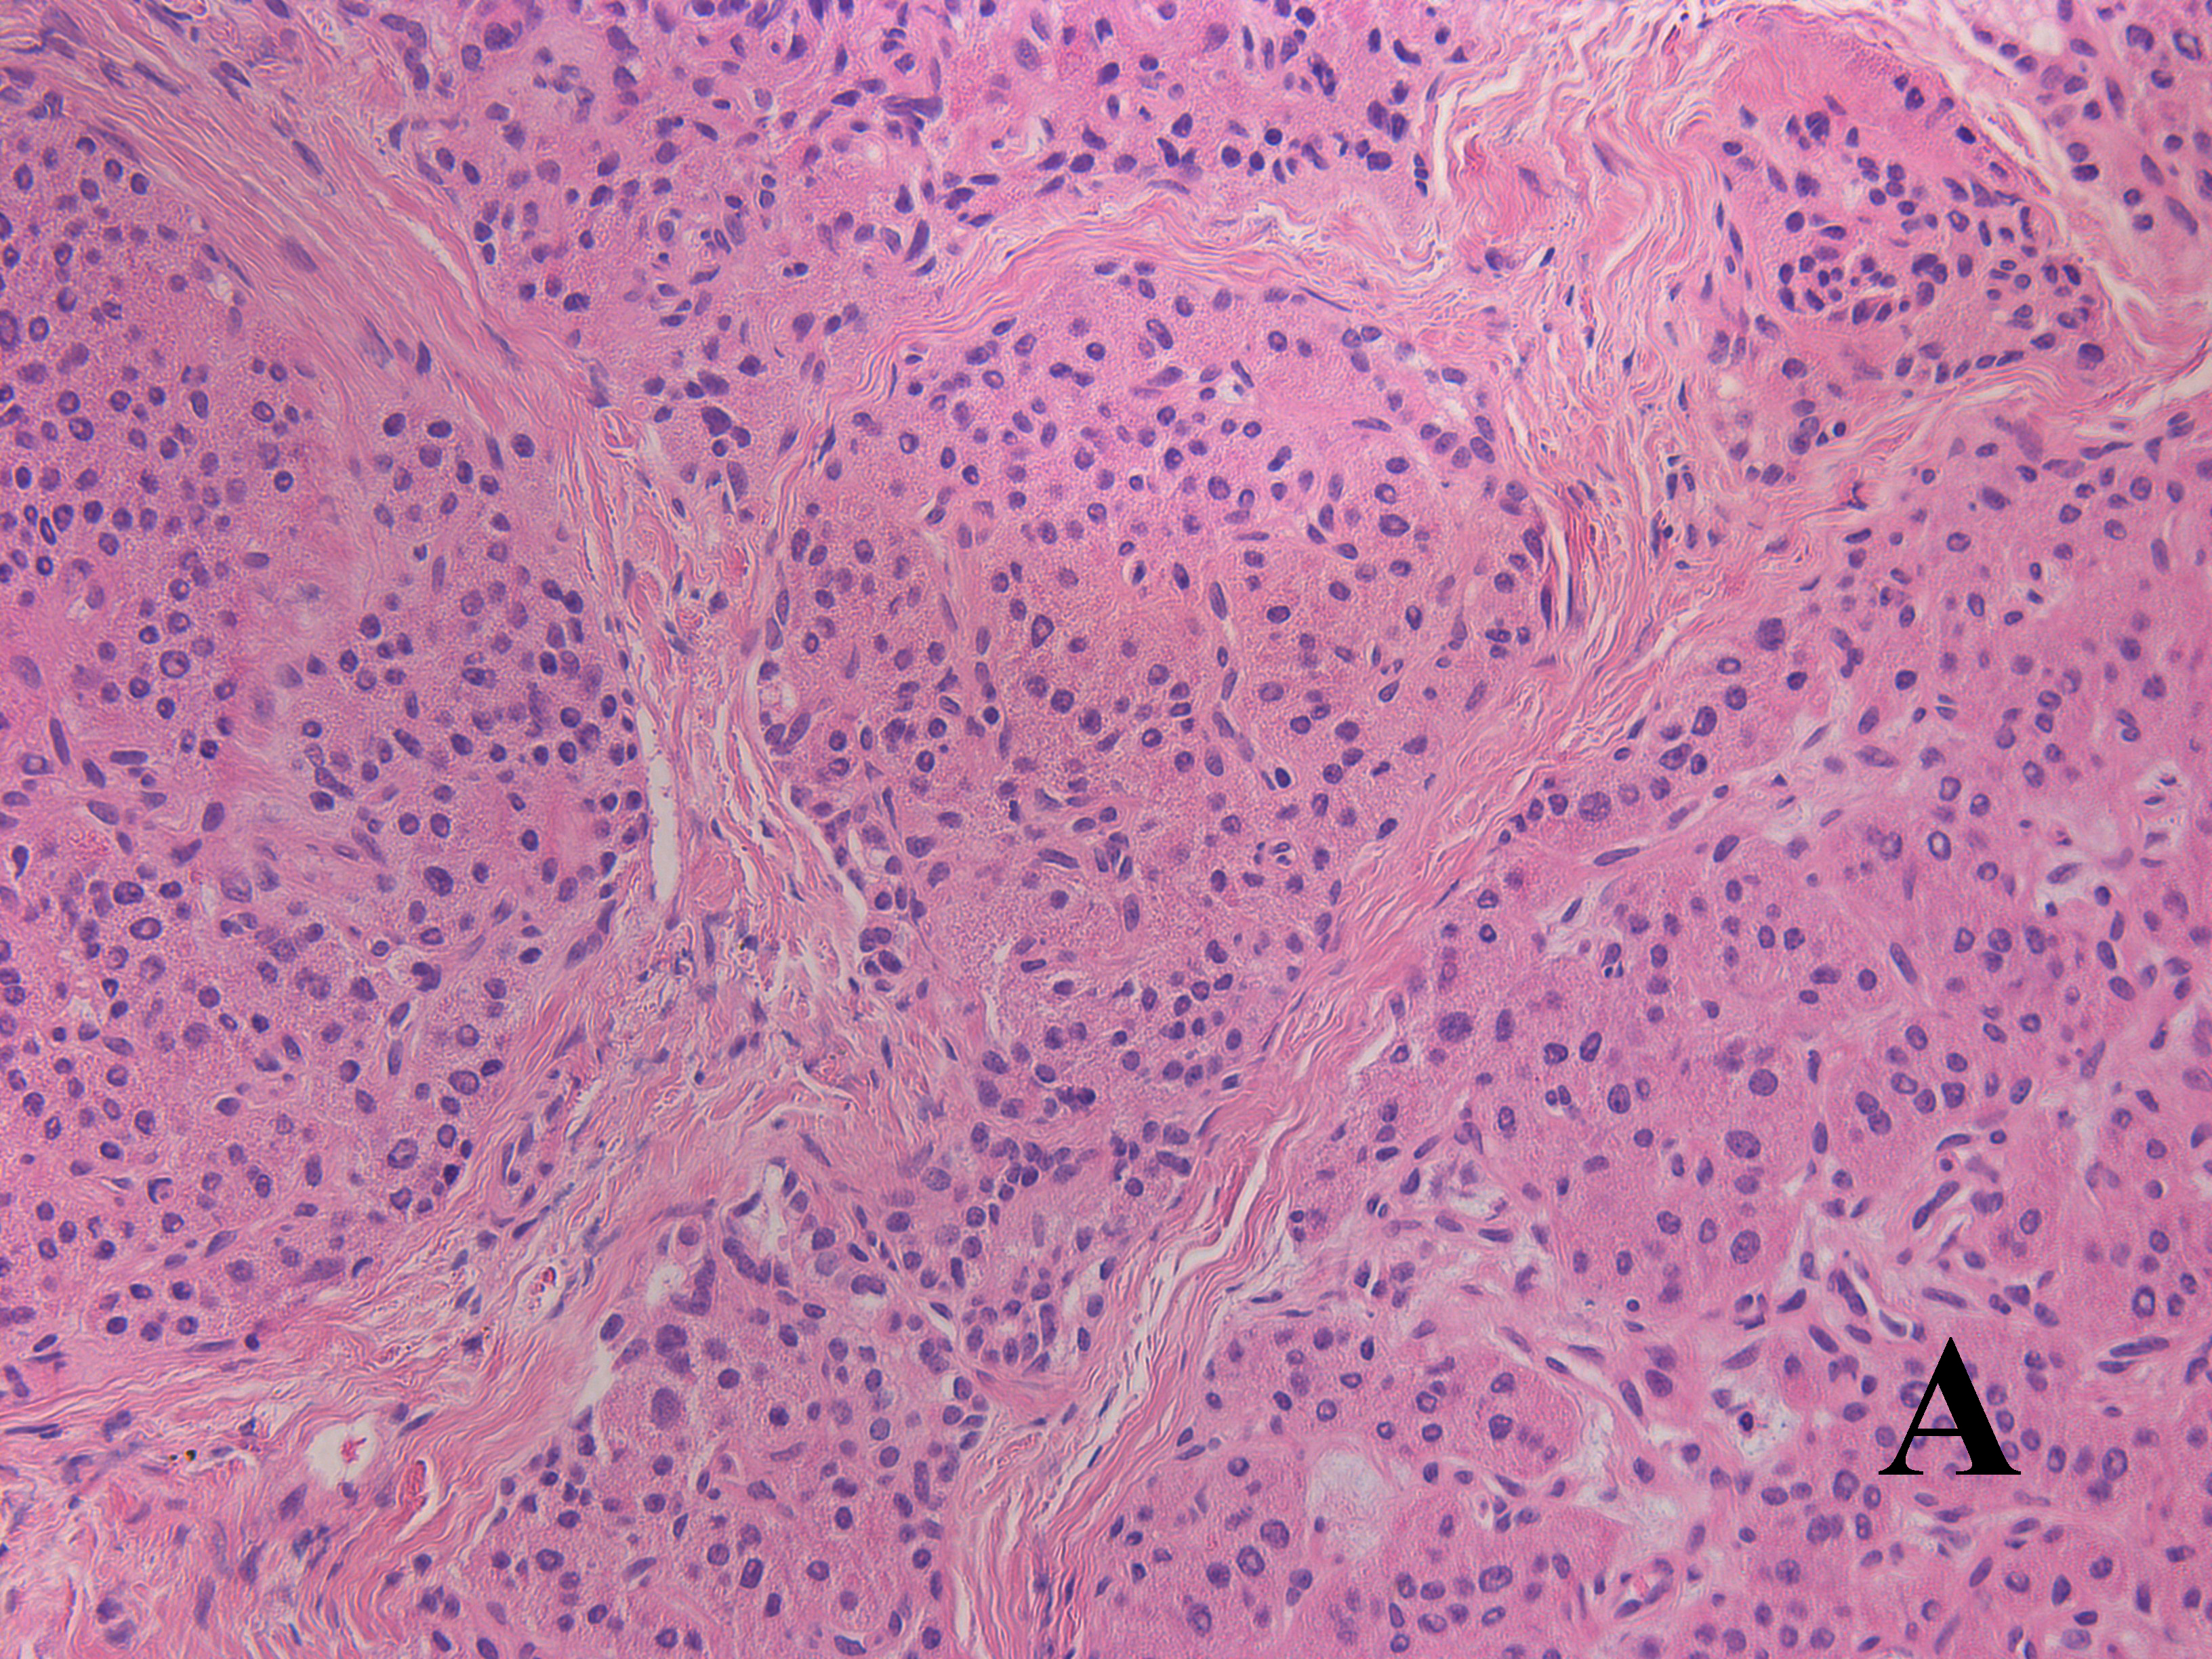

Несмотря на относительную эугликемию у части больных на фоне лечения октреотидом или диетотерапии, всем пациентам было проведено хирургическое вмешательство. Показания к оперативному лечению были обусловлены высоким риском развития гипогликемии на фоне пропуска приема пищи, тахифилаксией при применении октреотида, а также возможностью полного излечения после проведения резекции фокуса [23]. Большей части (25/31) детей выполнена резекция участка аденоматоза с проведением интраоперационной гистологической диагностики для оценки края иссечения (рис. 4). Проведение субтотальной панкреатэктомии пациентам с фокальной формой ВГИ было связано с отсутствием возможности проведения полной предоперационной диагностики, в частности ПЭТ/КТ с 18F-ДОФА на момент обследования.

Рис. 4. Гистологическое исследование ткани поджелудочной железы у пациента с фокальной формой ВГИ.

а – фокус гиперсекреции инсулина, метаплазия островков (окраска гематоксилином и эозином, ×20); б – выраженная экспрессия инсулина в фокусе при проведении иммунногистохимии; в – ткань поджелудочной железы вне фокуса гиперсекреции инсулина (окраска гематоксилином и эозином, ×200); г – низкая экспрессия инсулина вне фокуса при проведении иммунногистохимии.